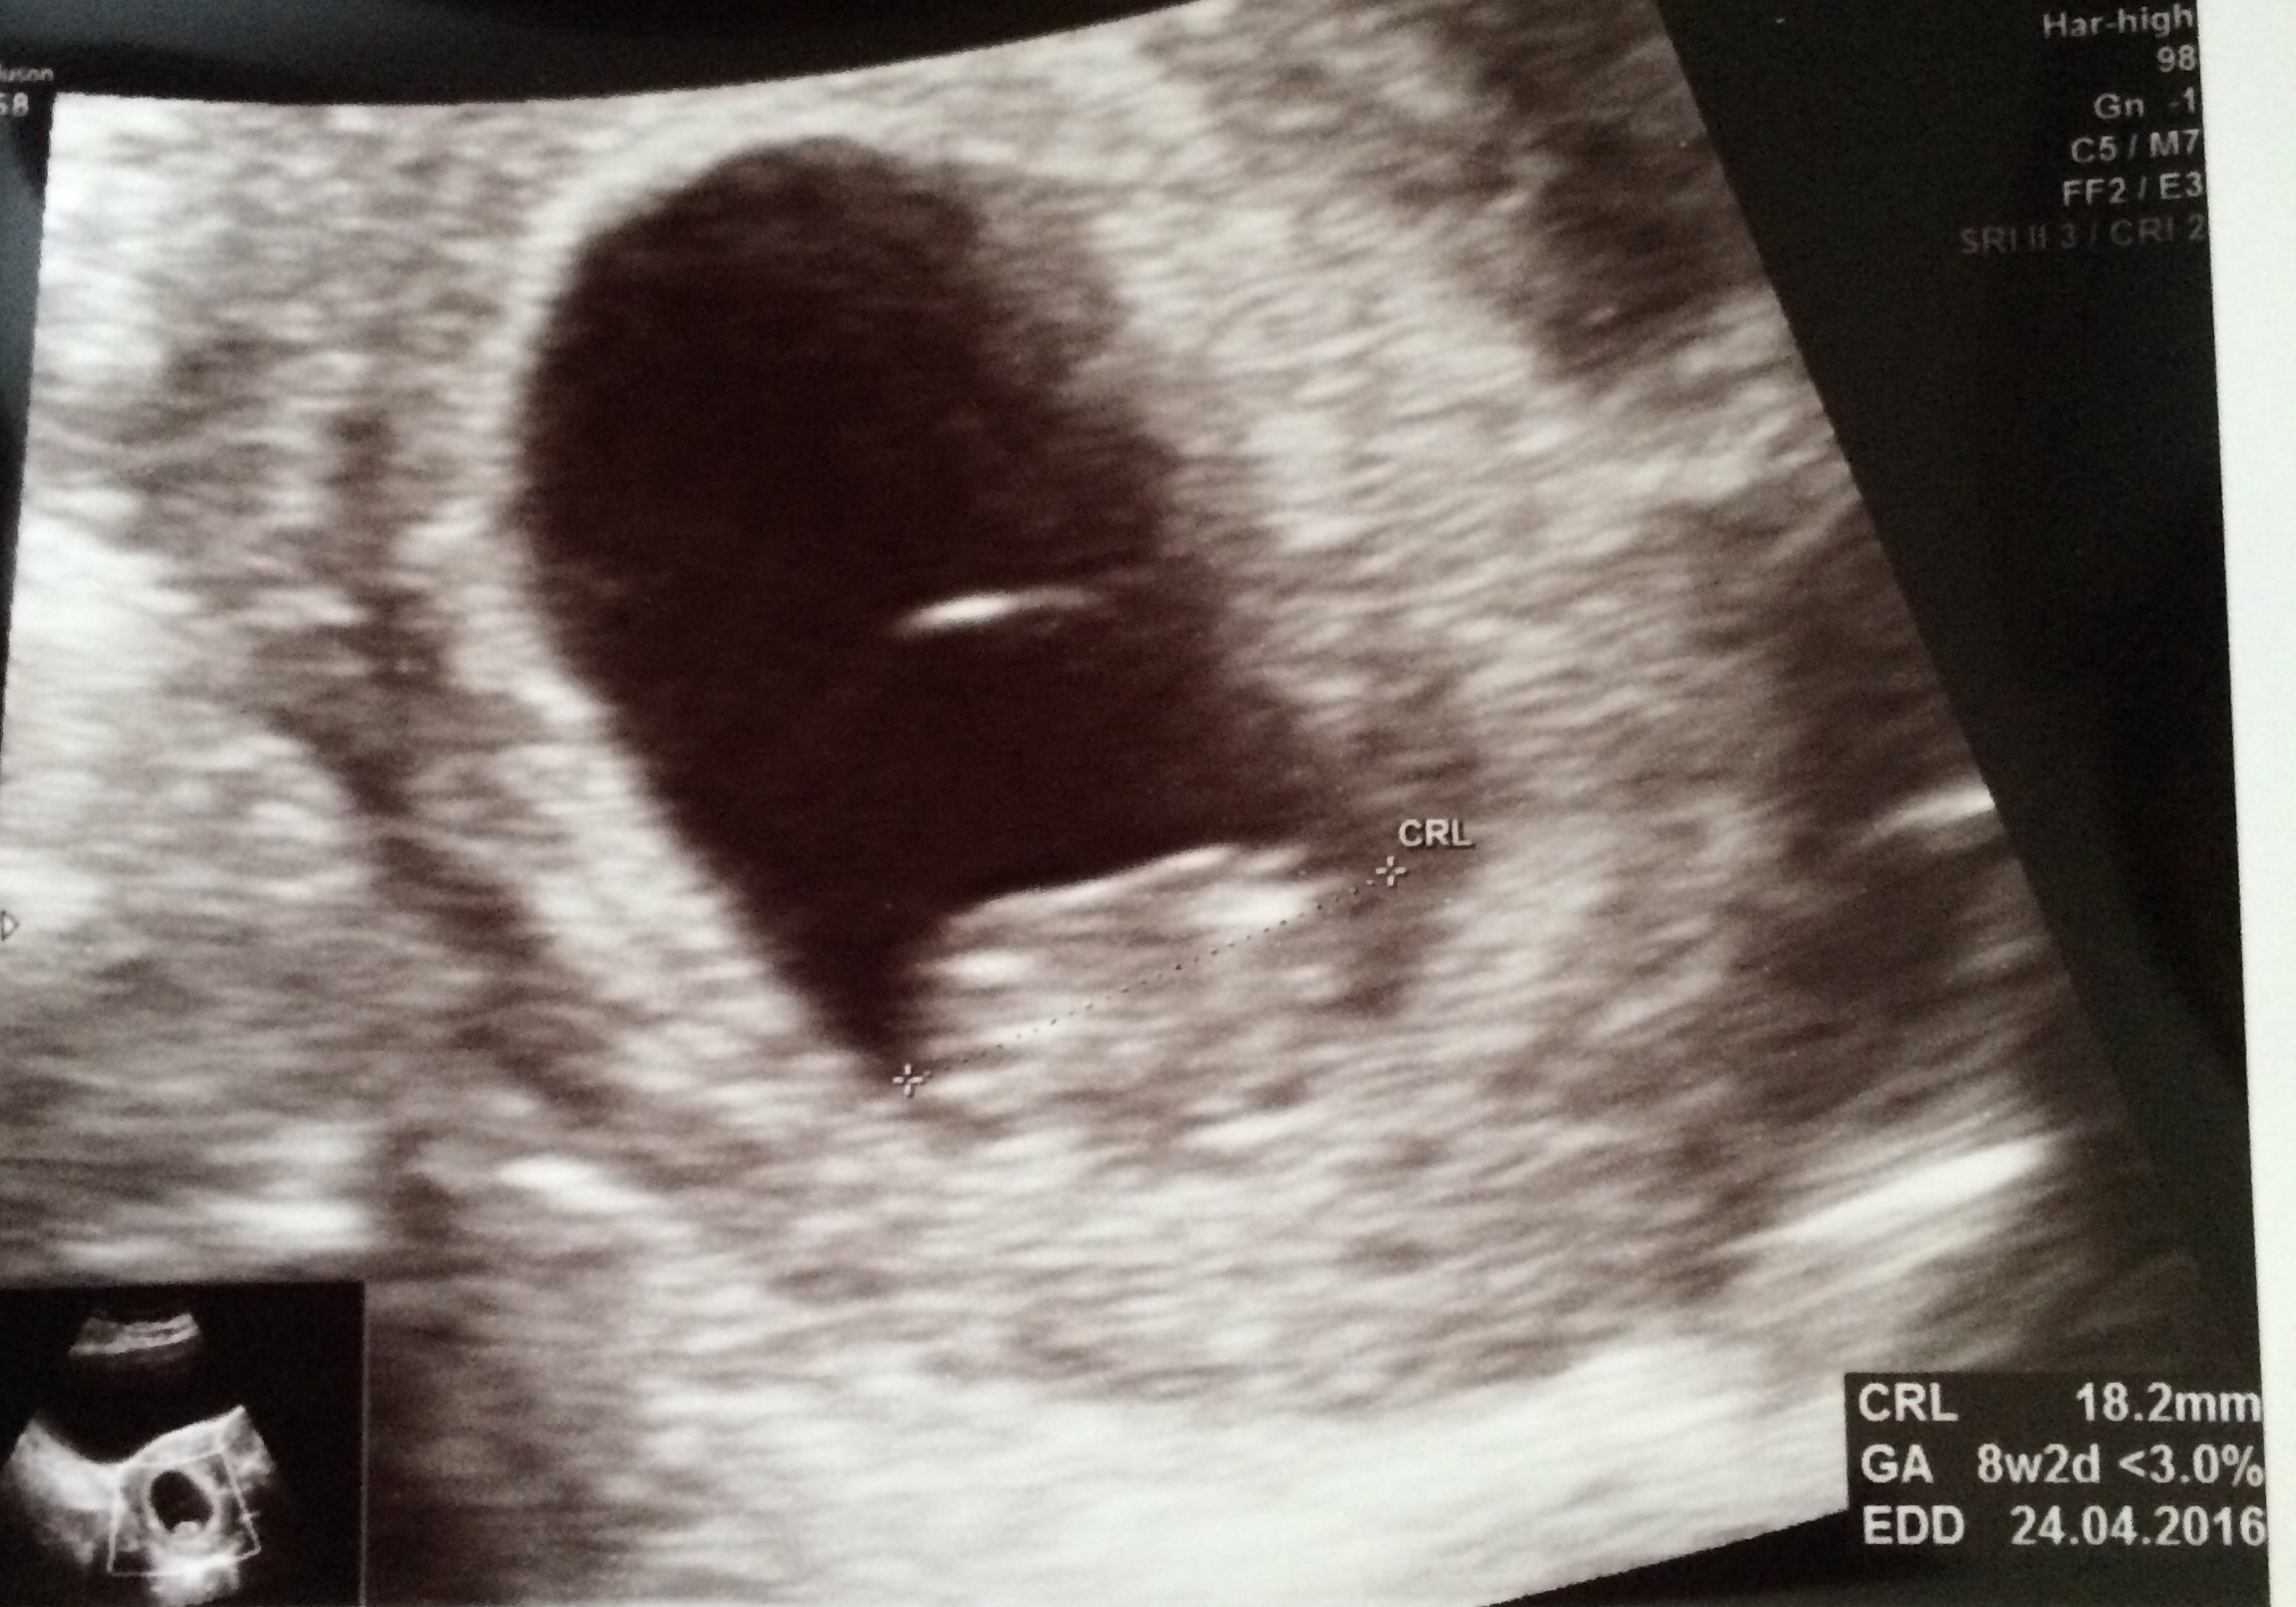

• Our peanut at 8w2d with a heart rate of 180 ❤️